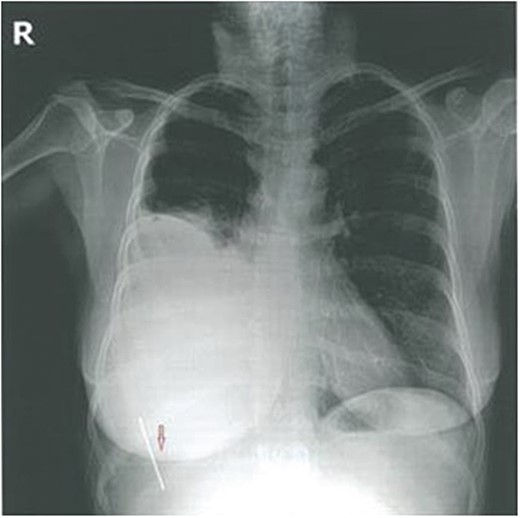

Laboratory investigations were within normal limits. The ECG was unremarkable. Chest X-ray showed the presence of a metallic image ∼5–6 cm long, located in the right hemithorax. There was a large hemothorax but no pneumothorax (Fig. 1). The investigation was complemented by a chest computed tomography (CT) that confirmed the presence of a metallic wire in the right pleural space.

She was placed in a left lateral decubitus position and a posterolateral thoracotomy in the fifth right intercostal space was used. The wire was removed without complications. Surprisingly, no injury was noted to any intervening abdominal structure intra-operatively. As a precaution, a 28-F chest tube was placed. There was no air leak or bleeding postoperatively and the tube was removed on the second postoperative day. The postoperative outcome was favorable and the patient was discharged on postoperative Day 4 with a normal chest radiogram (Fig. 2).